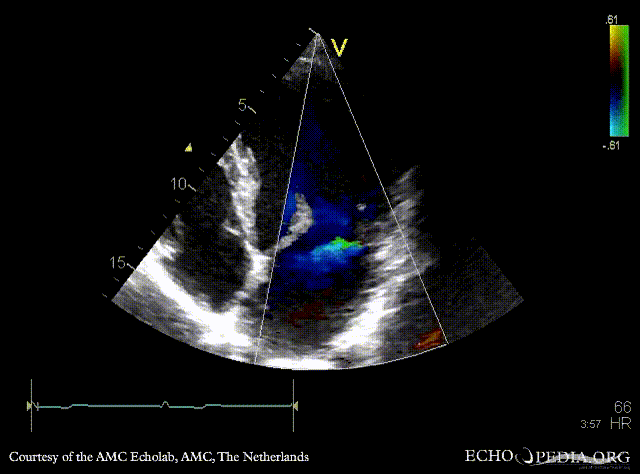

| PLAX with Color Doppler: mild mitral regurgitation